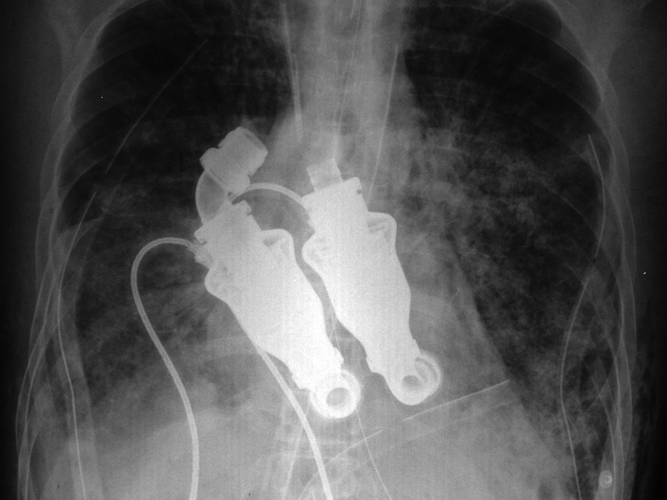

Heart: No Heartbeat Necessary

Courtesy of the Texas Heart Institute